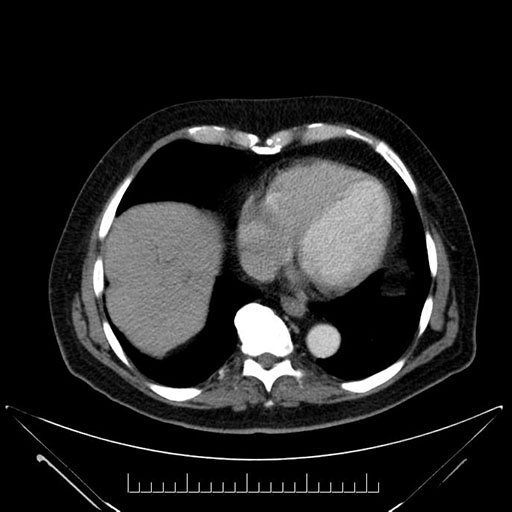

Axial - 3 months prior

Axial - stented